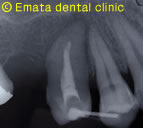

右上の虫歯が大きく、また右下の奥歯が根の病気が大きく抜歯になりました。 親知らずや内側に倒れた不必要になった歯があったので移植をおこないました。